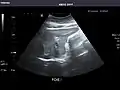

Kidneys: Right and left kidneys measure 11.5 cm and 12 cm in length respectively. No hydronephrosis. Small left lower pole kidney cyst.

Left kidney